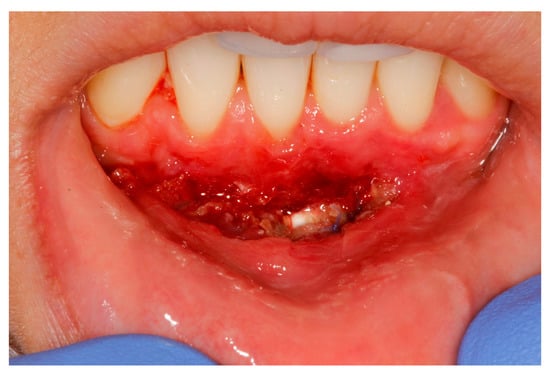

- (a)

- deep partial thickness incision (blade parallel to the periosteum) made at the level of the external insertion of the frenulum;

- (b)

- elimination of superficial mucous tissue and muscle of the frenulum;

- (c)

- a series of detached points with periosteal anchorage for the apical positioning of the lining mucosa of the lip and the second intention healing of the exposed periosteum.